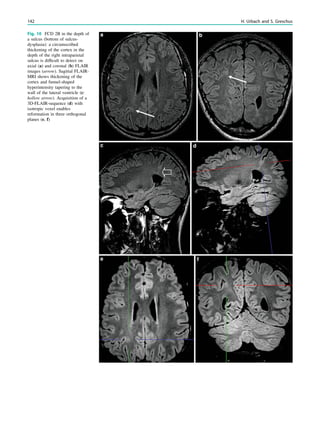

Fig. 1 Digital photogram of the brain surface before placement of a

Fig. 2 Epileptogenic lesion and symptomatogenic zone. A 40-year-

(a, arrow). Simultaneous video and EEG recordings from interhemi-

Clinical symptoms start around 1 s afterwards (d, asterisk)